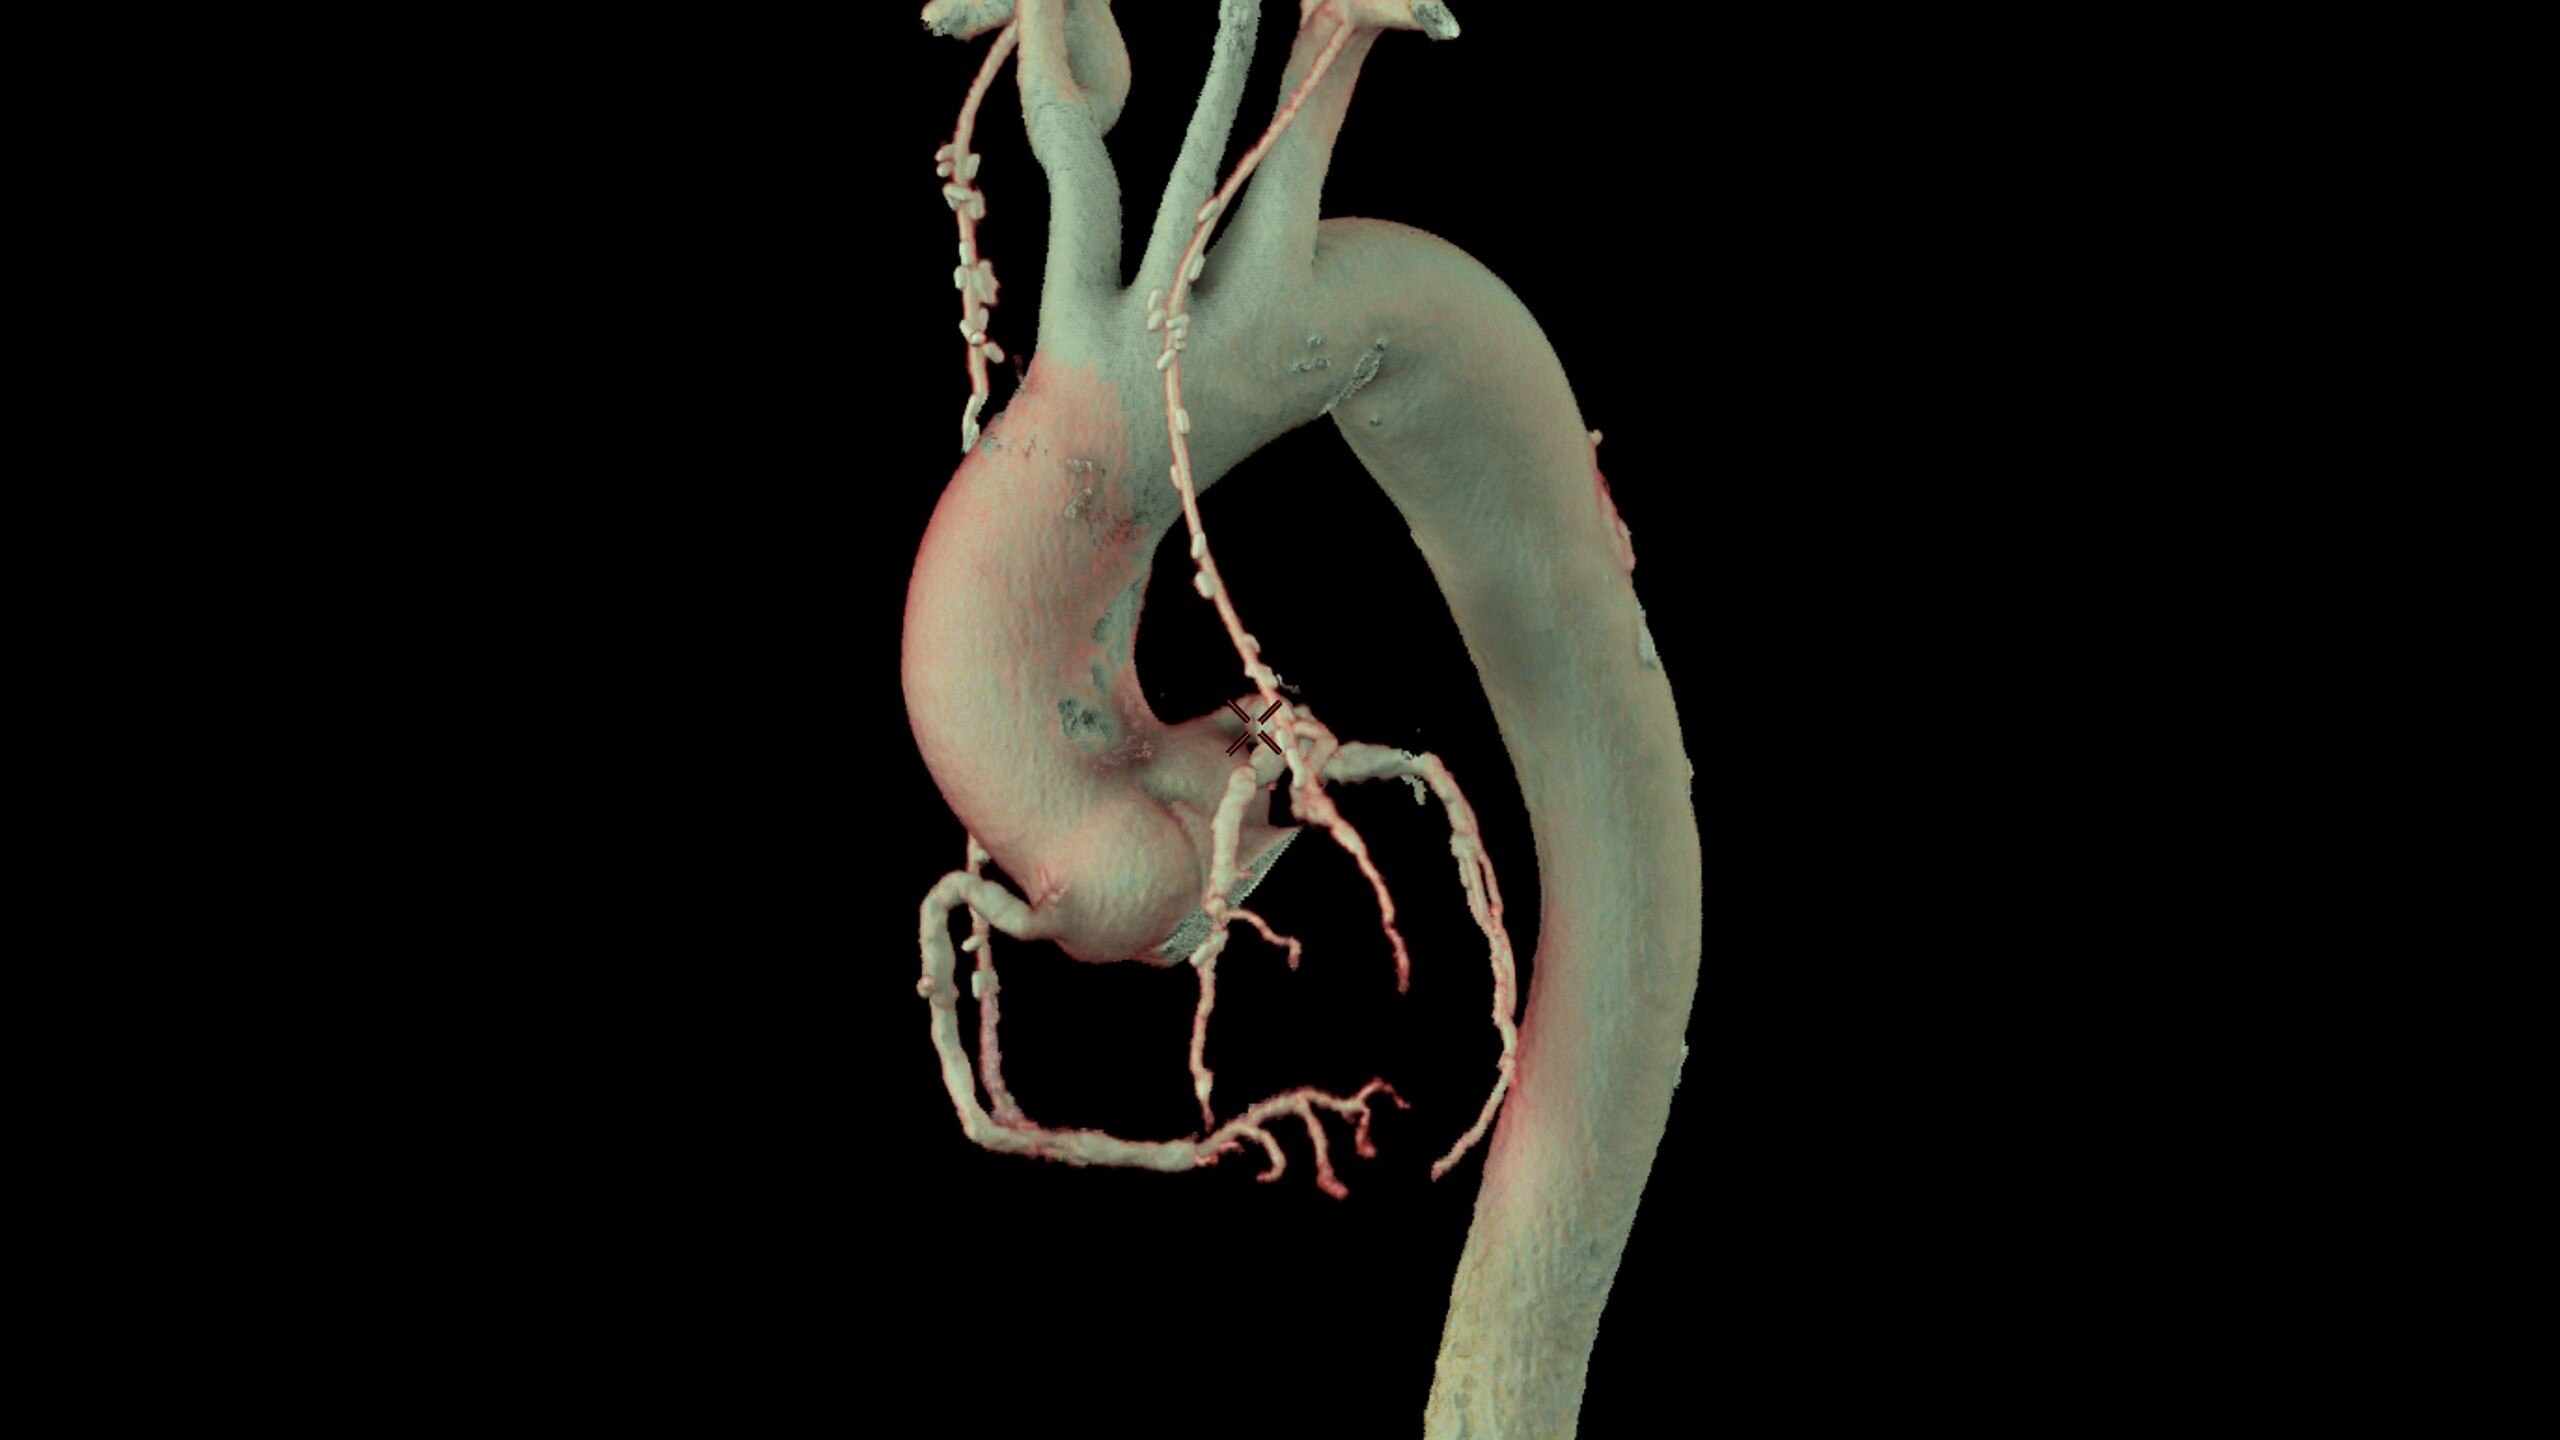

• Relative perfusion color codes and quantifies percent of

hypo-dense areas of myocardium with four selectable

color maps and fusion overlays with the coronary tree

• Automatic extraction of the left ventricle across all

phases and the automatic detection of systole and

diastole delivers calculated ejection fraction and stroke

volumes